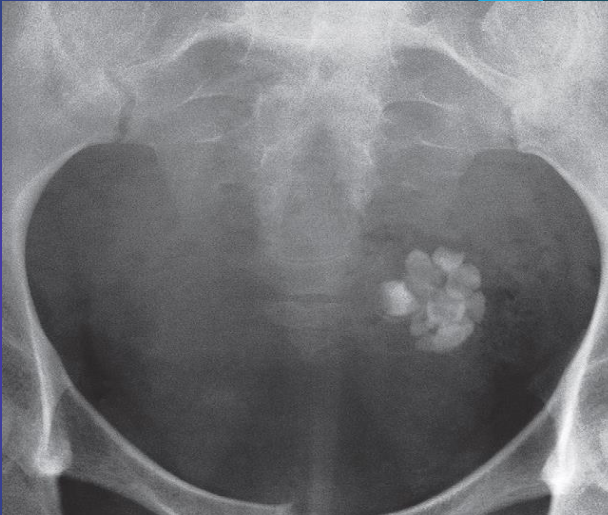

Calcified Uterine Leiomyoma

Plain radiograph:

- Calcification in a large uterine fibroid